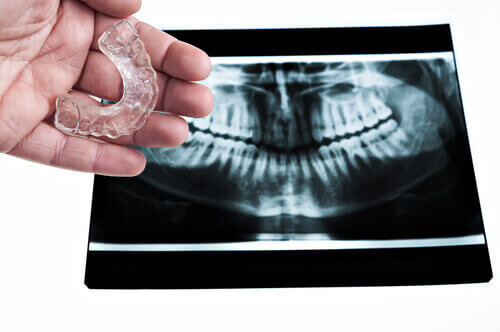

Een mogelijke oplossing om het knarsen te vermijden is ‘s nachts een mondstuk inbrengen dat het over elkaar schuiven van de tanden tegengaat. Het beschermt de tanden eveneens tegen te hoge druk. Ook een ontspannende massage van de gezichtsspieren, de nek, hals en schouders kan soelaas brengen.